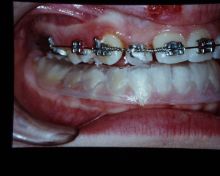

Un incisivo laterale superiore dx sul palato e' stato posizionato sul vestibolo, dopo recupero dello spazio necessario per l'allineamento.

Durata della terapia 14 mesi.

TAG: Incisivo lalerale dx palato